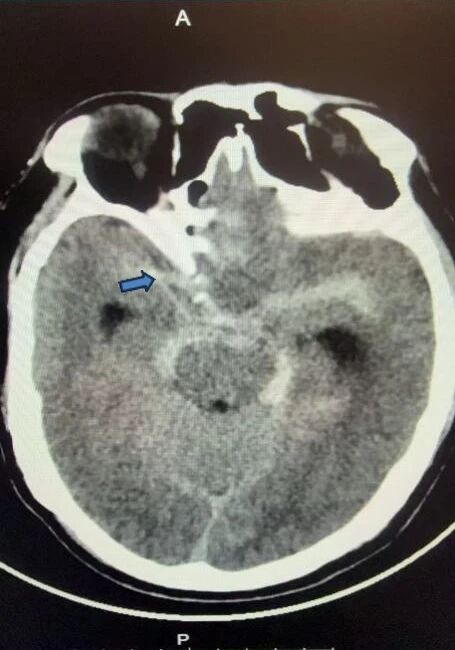

一位63岁的男性,因“突发头颈部疼痛2小时”入院。入院查体:轻度意识障碍,头颅CT检查提示颅内蛛网膜下腔出血(图1),头颈部血管CTA检查未见明显异常。经神经外科团队科内讨论后仍不排除患者存在脑血管病变可能,遂行全脑脑血管造影术,术中发现存在前颅底硬脑膜动静脉瘘,眼动脉供血,经海绵窦、岩下窦向颈内静脉引流(图2)。曾实主任医师立即组织科内讨论,本例患者的动静脉瘘位于前颅底,供血眼动脉分支迂曲细小,介入栓塞剂弥散到位困难,存在误栓塞视网膜中央动脉导致失明风险。因此,确定手术策略为显微手术切除,暴露前颅底全切瘘口。在麻醉科和手术室护理团队的全力配合下,曾实主任医师主刀、熊海兵主治医师协助,在全麻显微镜下实施硬脑膜动静脉瘘切除术(图3)。手术顺利,术中荧光造影显示瘘口完全消失。术后转入神经外科监护室,在神外医护团队的精细管理下,患者术后1周痊愈出院。

图1